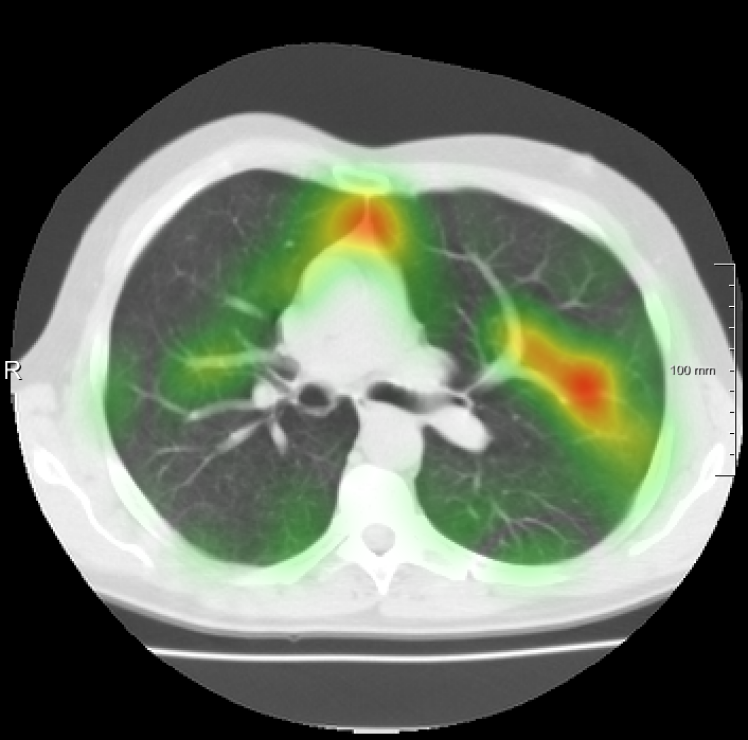

For the DIR-Lab-4DCT database, a comparison between RegNet and affine, B-spline (three resolutions), an advanced conventional registration method using sliding motion (Berendsen et al., 2014) and three other CNN-based methods (Eppenhof and Pluim, 2018; de Vos et al., 2019; Sentker et al., 2018) is available in Table IV. It can be seen that training with “S+M” improved performance slightly with respect to just “S”. Adding the respiratory motion category improved performance substantially, as these are inhale-exhale pairs; this is predominantly caused by the patients where the TRE after affine registration was still quite large. An example visualization is also available in Fig. 5(f), showing that adding the respiratory motion category can align images better in the diaphragm region. The advanced conventional registration method that leverages sliding motion (Berendsen et al., 2014) is still better than RegNet. Note that RegNet was not trained on the DIR-Lab-4DCT data, similar to Eppenhof and Pluim (2018); Sentker et al. (2018). However, de Vos et al. (2019) and Eppenhof and Pluim (2018)-DIR methods were trained on the same database but using cross-validation to report the results. Also note that the results reported in Sentker et al. (2018) are averaged over all phases of DIR-Lab-4DCT (T00 to T10), while the results of other CNN methods (including RegNet) are reported between the maximum inhale and maximum exhale phase (T00 and T50). These reported results are therefore likely somewhat better than the results for T00 and T50 only.